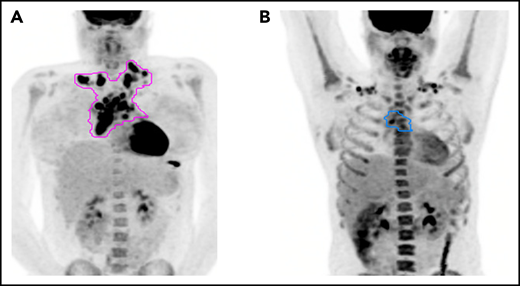

For relapses, the following images were reviewed in a central location: baseline imaging at diagnosis to determine initial site(s) of disease; interim and postchemotherapy functional (PET1 and PET3) and anatomic imaging (CT); a radiation treatment plan, if applicable; and imaging at relapse. Sites of recurrence were categorized as initial, new, or both, and for the PET1+ subgroup as PET1+ site or initially involved site beyond the PET1+ site (Figure 1). The Kaplan-Meier method was used to evaluate progression-free survival (PFS) by PET1, and the log-rank test was used for comparisons between survival curves.

Pattern of relapse definitions. (A) Theoretical outline (pink) of initial site of disease based on the prechemotherapy PET/CT scan. A relapse within the outlined region would have been categorized as a relapse in the “initial site” of disease. A relapse outside of the outlined region would be considered a “new site” of relapse. (B) Theoretical outline (blue) of fluorodeoxyglucose-avid residual disease greater than the mediastinal blood pool on PET/CT after 1 cycle of AVPC. For PET1+ patients, a relapse within the blue region would be considered a relapse at the “PET1+ site,” whereas a relapse outside of the blue region but within the pink region from panel A would be considered “initial site beyond the PET1+ site.”